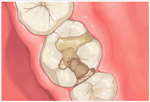

アメリカのヒューストン発のDoc's Best Cements(ドックベストセメントまたはドックスベストセメント)により痛くない、削らない、神経を取らない治療が可能になりました。(従来の保険治療で行うような予防的な拡大処置としてむし歯以外の健全な歯質を削らないということです。

まったく歯を削らないという意味ではありません。) ドックベストセメントは、Dr.Fraserが1990年に開発したミネラルを含んだ銅セメントです。

ドッグベストセメント治療は、銅、酸化亜鉛、酸化チタン、リン酸、水酸化アルミなどを主成分とする素材を使います。鉄(Fe)イオンと銅(Cu)イオンのコンビネーションによる殺菌力が、むし歯に効果的に作用することで、むし歯菌に侵された歯の象牙質の無菌化を促すという大きな働きがあります。

メリット一般的なむし歯治療と違い、ドッグベストセメント治療は必要以上に歯を削らないで済みますので、歯を削る違和感もなく、痛みを感じないので、麻酔注射も必要ない場合がほとんどです。

ドッグベストセメントの鉄(Fe)イオンと銅(Cu)イオンのコンビネーションによる殺菌力で患部を殺菌することで、神経を残せる可能性が高くなります。

むし歯菌に侵されている歯の内部の象牙質をドッグベストセメントの鉄(Fe)イオンと銅(Cu)イオンで殺菌することで、歯の象牙質部分の再石灰化を促します。